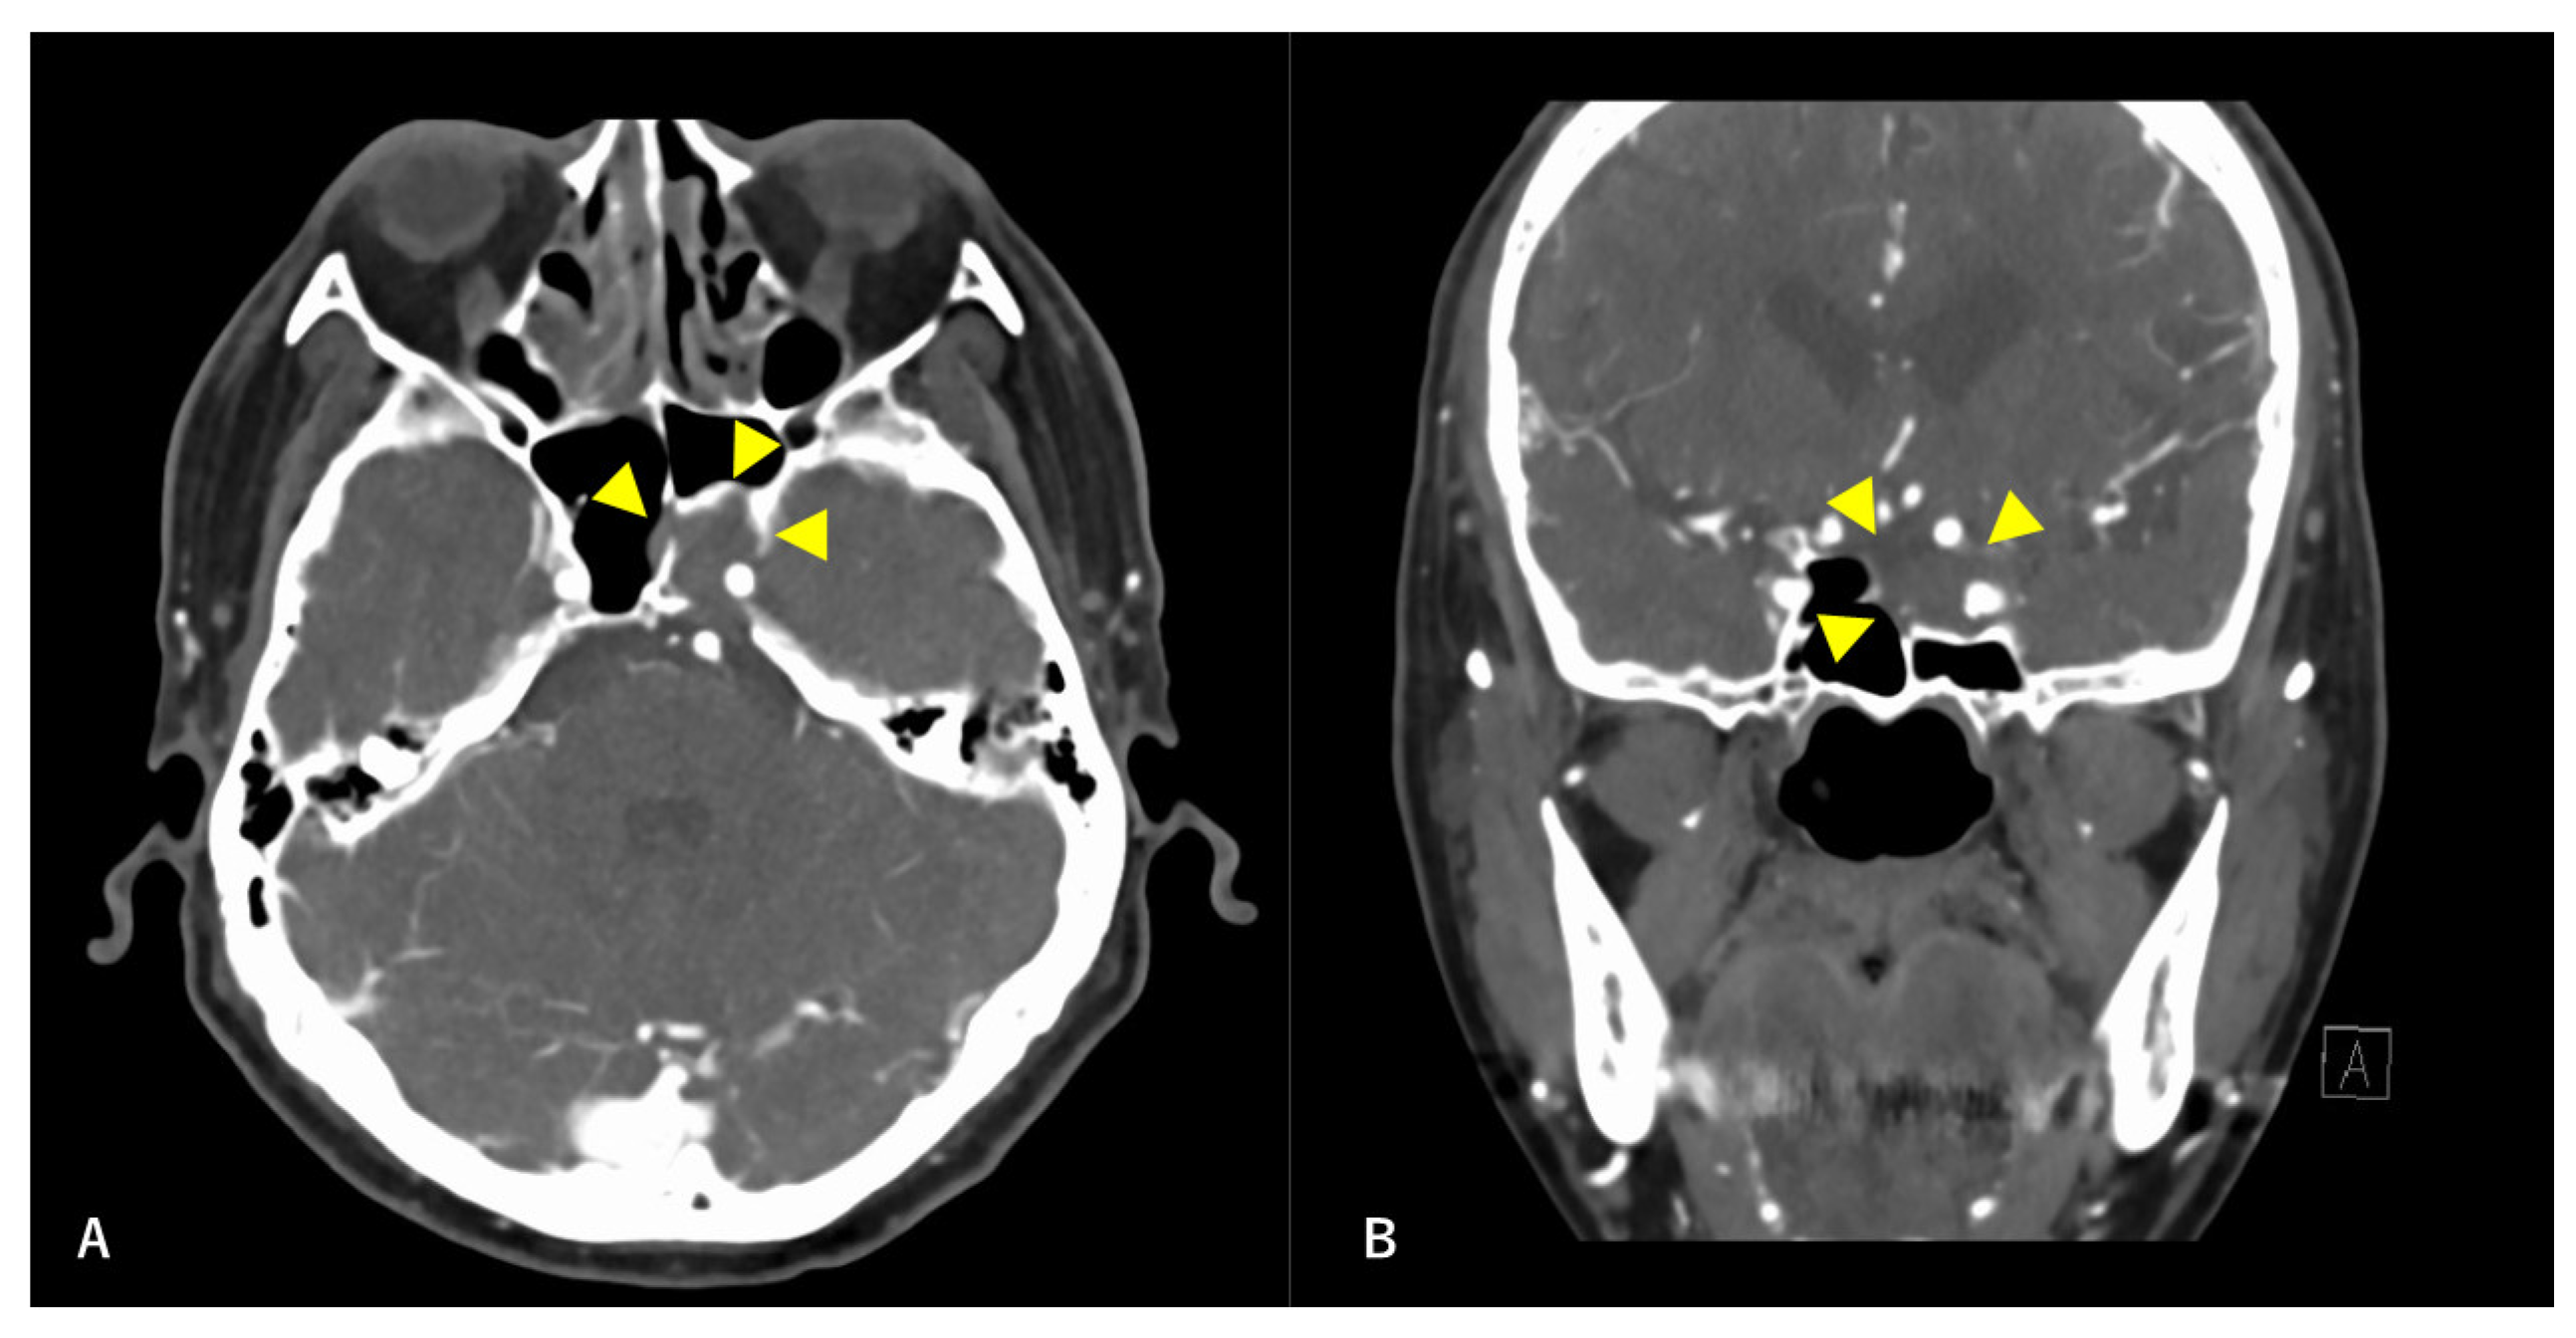

Figure 4. Postoperative T1-weighted contrast-enhanced MRI findings. Axial section (A) and coronal (B) images are shown. The tumor is confirmed to be resected along with the ICA. Arrowheads indicate the site of tumor removal.

A multidisciplinary team of otolaryngologists and neurosurgeons performed a complete resection of the tumor using a simultaneous combined transcranial and transnasal approach that utilized high-flow radial artery bypass between the M2 segment of the left middle cerebral artery (MCA) and the left cervical external carotid artery with an additional superficial temporal artery–MCA bypass. The margin of tumor resection was determined by a rapid intraoperative diagnosis to confirm the tumor extent. The ICA was trapped under blood flow preservation bypasses, enabling complete resection of the tumor along with the ICA (Figure 4). The ocular artery and cranial nerves III–VI were preserved. The skull base was reconstructed using two layers of the temporalis muscle and a vascular pedicle nasoseptal flap. Magnetic resonance angiography was performed immediately after the surgery, indicating adequate blood flow through the bypasses (Figure 5). The postoperative immunohistochemistry results were positive, similar to the biopsy immunoprofile (Figure 6). In addition, there were no S-100 protein-positive sustentacular cells around the tumor cells. Differentiating between high-grade ONB and neuroendocrine tumors is sometimes difficult; the tumor was eventually diagnosed as NEC, based on the absence of sustentacular cells and the absence of morphological findings such as Homer–Wright rosettes (Figure 6D).